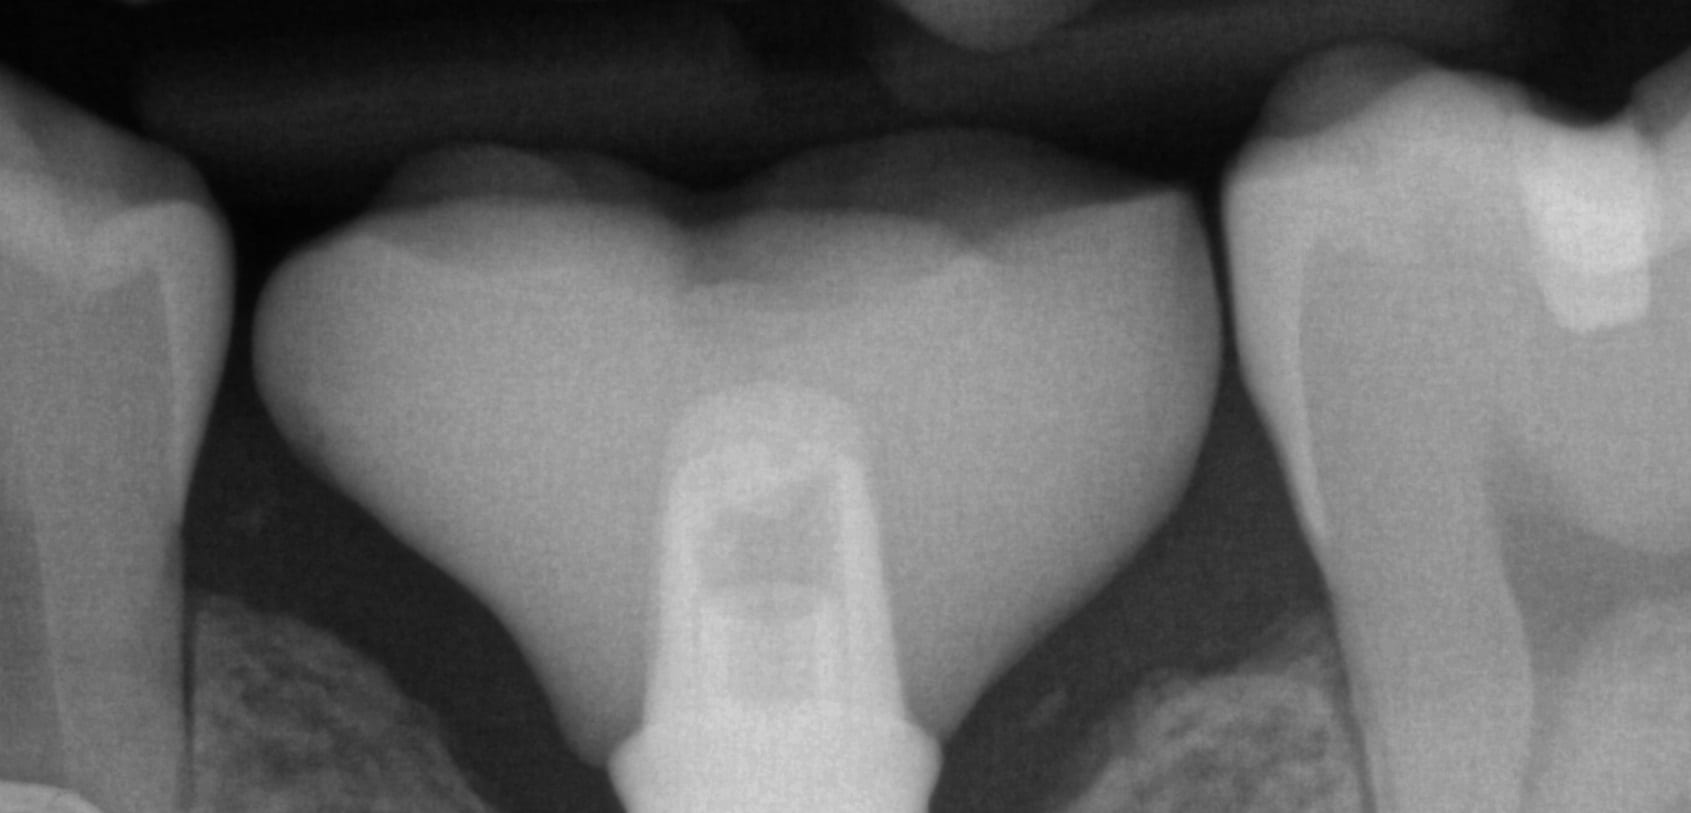

August 15, 2019In this article, we feature an upper left lateral crown that needed to be replaced due to recurrent decay. While the patient was getting numb, we defined the job description […]